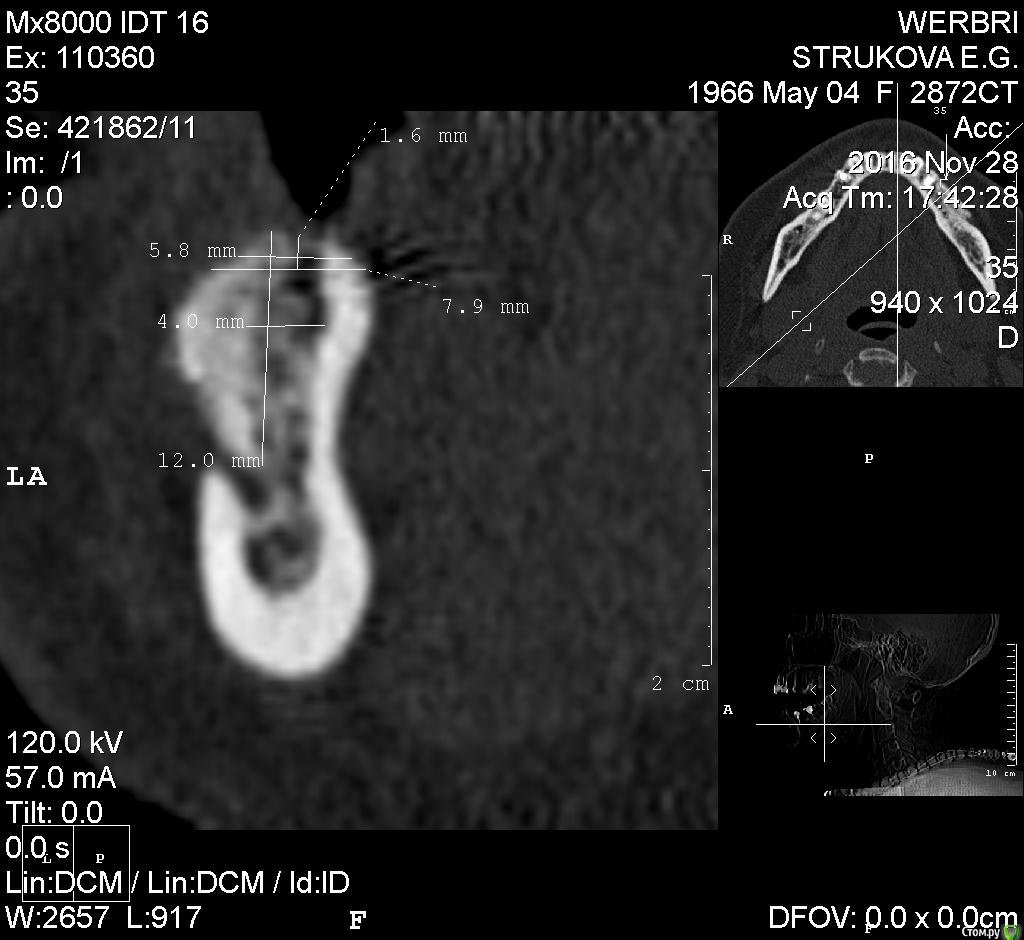

kamranchick Опубликовано 2 мая, 2016 Автор Поделиться Опубликовано 2 мая, 2016 ну я указал 3 сегмент, 3 винта, следовательно удаление 5 го зуба, установка имплантатов в область 35 36 и 37 Ссылка на комментарий

dantist_movani Опубликовано 2 мая, 2016 Поделиться Опубликовано 2 мая, 2016 Ось имплантата в проекции 3.7 слишком язычная, так же имплантат устанавливали? Ссылка на комментарий

kamranchick Опубликовано 1 февраля, 2017 Автор Поделиться Опубликовано 1 февраля, 2017 Аугментата пожалели мне кажется, объёма не особо добавится. Почему винты сразу не захотели? Вроде кости много.Побоялся что если что то пойдет не так то придется все выгребать))Кости если честно не пожалел, не знаю куда он ушел, была ауто кость 2 грамма gen os и 0 5 альфа био графта Ссылка на комментарий

kamranchick Опубликовано 30 января, 2018 Автор Поделиться Опубликовано 30 января, 2018 скальпелем 11 и тонкими фрезами Альфа био) Ссылка на комментарий